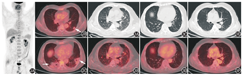

转移灶的代谢活性通常与原发灶相关。肺内病变的代谢不高,提示原发灶可能是代谢不高的恶性肿瘤甚至是良性肿瘤。肺原发代谢不高的肿瘤需考虑肺黏液腺癌,该病是肺腺癌的一种特殊类型,发病率低,仅占肺腺癌的0.14%[1]。肺黏液腺癌多见于老年患者,临床表现无特异性,病变易发生周围种植转移或沿气道进行播散,CT上常表现为不规则斑片实变或结节肿块影,有时大体形态类似肺炎。由于肺黏液腺癌的分化程度较好、肿瘤组织富含黏液而细胞密集程度相对较低[2],故PET显像可表现为代谢不高(图2)。本例患者肺内病变的代谢活性虽然与之相似,但所有结节的CT表现为典型肺血行转移瘤的特点,缺乏肺原发肿瘤的形态特征,因此不考虑该诊断。肺外原发代谢不高的肿瘤,如甲状腺癌(图3A,图3B)、乳腺癌(图3C,图3D)、肾癌(图3E,图3F)、肝癌、消化道肿瘤等,也可有与本例相近的肺转移表现。因此,需要对上述部位从CT形态学(密度及形态的变化)、PET代谢活性、原发灶周围区域等几个方面进行仔细观察,必要时进一步结合临床资料,以明确有无其他隐匿性病变。例如,甲状腺癌需要观察甲状腺密度是否均匀、是否有结节,气管周围、锁骨上下区有无肿大淋巴结;乳腺癌需要观察双侧乳腺是否有结节,腋窝有无肿大淋巴结;肾癌的代谢可不高,由于受到放射性尿液的干扰,因此需要观察肾的形态及密度是否有异常,以及肾周有无肿大淋巴结、肾静脉和下腔静脉有无癌栓形成;肝癌是否有肝硬化表现,肝是否有可疑占位,患者有无乙肝病史;消化道肿瘤常被肠道的生理性摄取掩盖,但是由于易发生淋巴结转移、腹腔种植转移和肝转移,仔细观察上述常见转移部位可以辅助判断是否存在隐匿的肿瘤。通过观察本例患者以上脏器及相应的常见转移部位,并没有发现异常的CT表现或PET代谢。